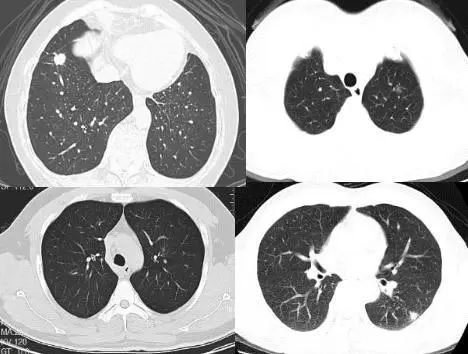

实性肺结节(solid nodule),间质血管都看不见(左上图),亚实性肺结节(subsolid nodule)包括纯磨玻璃结节(pure ground-class nodule,pGGN)(左下图),还有混杂性结节(mixed ground-glass nodule,mGGN),也称部分实性结节(part solid nodule),表现为间质样改变,中间实性,周围是磨玻璃样。